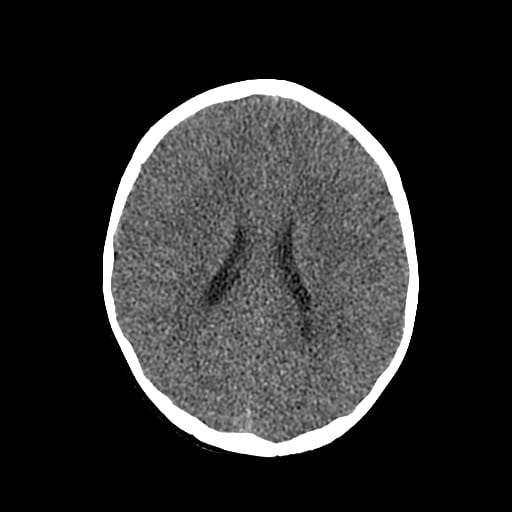

Age: 1

Sex: Male

Indication: Fall